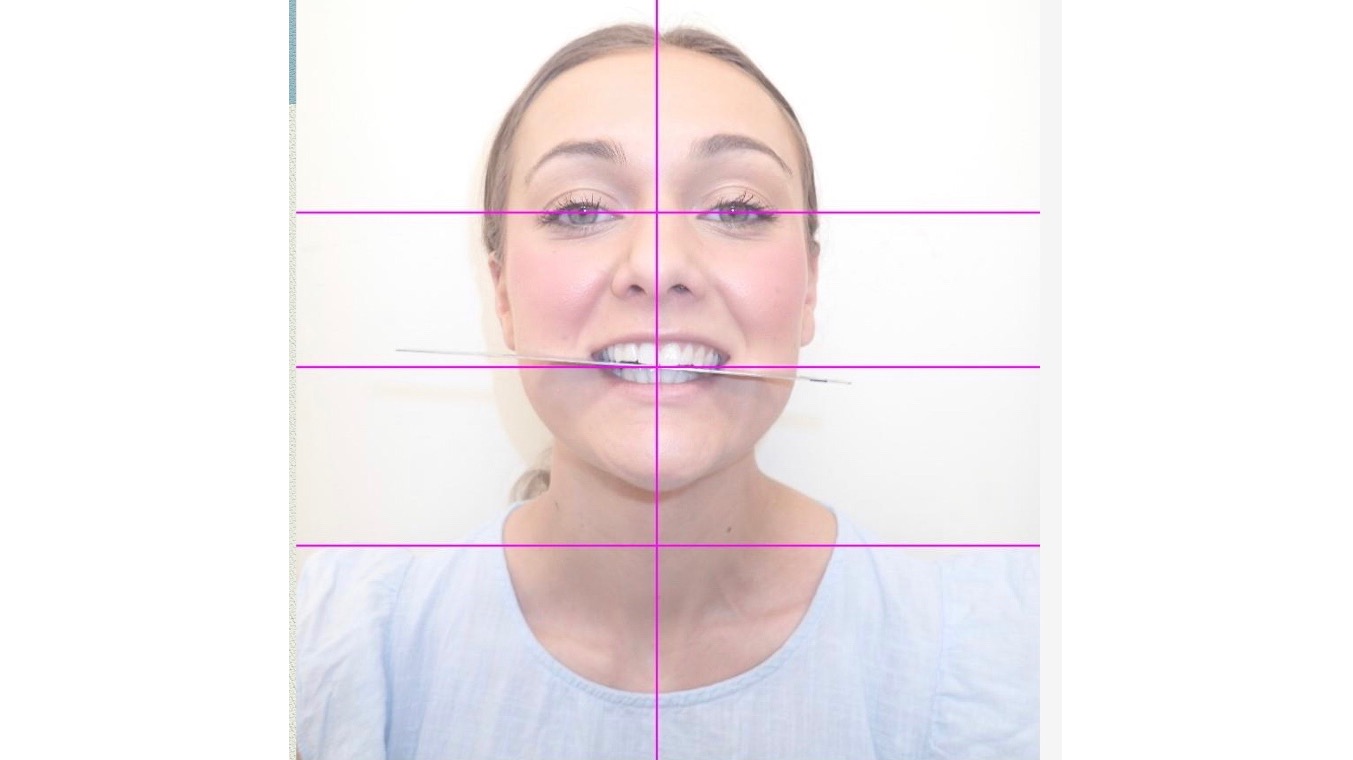

I had a dental procedure take place in 2019, which has cost me 4 years of my life living in chronic pain, misplaced jaw, breathing issues, fatigue and basically bed ridden terms. After many treatments that haven’t helped, many referrals to medical professionals, I am now booked in to have Double Jaw Surgery in July 2024 to fix my misaligned jaw, my uneven non existent bite, my headaches, neck issues as well as most importantly my breathing / airways.

I had a dental procedure take place in 2019, which has cost me 4 years of my life living in chronic pain, misplaced jaw, breathing issues, fatigue and basically bed ridden terms. After many treatments that haven’t helped, many referrals to medical professionals, I am now booked in to have Double Jaw Surgery in July 2024 to fix my misaligned jaw, my uneven non existent bite, my headaches, neck issues as well as most importantly my breathing / airways.